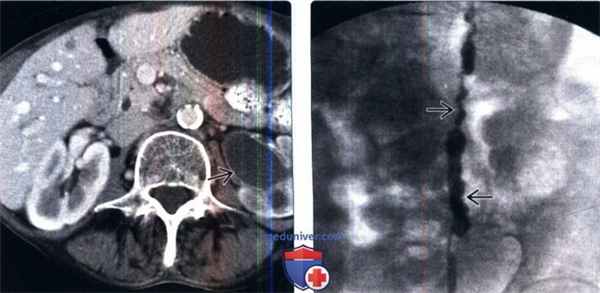

(Слева) КТ с контрастированием, аксиальный срез: у пожилого мужчины с пиурией и лихорадкой определяется левосторонний гидронефроз и отсроченная нефрограмма. Стенки левого мочеточника и лоханки утолщены и накапливают контраст, что указывает на воспаление. На нефростомии был обнаружен пионефроз.

(Справа) Антеградная пиелография: у этого же пациента определяется неправильный контур левого мочеточника. Эти признаки характерны для уретерита. Спазм мочеточника может также играть роль у этого пациента, поскольку имеются признаки активной инфекции.

По данным спиральной компьютерной томографии, выявлены множественные конкременты обеих почек, а также кальцинированные лимфатические узлы брыжейки тонкой кишки (рис. 1).

Рисунок 1. КТ после нефростомий. Множественные камни почек и кальцинированные лимфоузлы брыжейки

Figure 1. CT-scan after nephrostomy. Multiple kidney stones and calcinated mesenteric lymph nodes

При антеградной пиелоуретерографии отмечается нарушение пассажа контраста по мочеточникам с наличием множественных сферических внутрипросветных дефектов наполнения (рис. 2).

Рисунок 2. Антеградная пиелоуретерография

Figure 2. Antegrade pyeloureterography